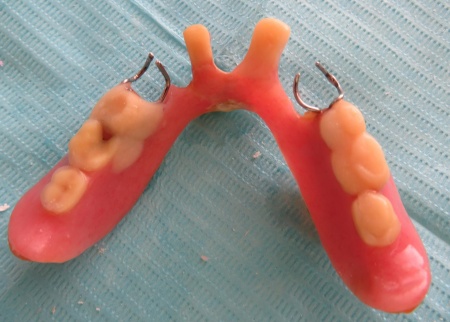

治療後

| 行ったご提案・治療内容 | 今回は、破損していたクラスプを新しく作り直し、入れ歯を修理する方法を提案しました。 これまでも同様の修理を行っているため、患者さまも修理の流れをよく理解されています。 入れ歯を修理する場合は、入れ歯をお預かりして数日から1週間ほどお時間をいただくのが一般的ですが、当院では歯科医師が院内でクラスプを作製できるため、約1時間で修理をすることが可能です。 ただ長期的な使用状況によっては、再度調整や修理が必要になることもあります。 修理方法のメリットとデメリットをお伝えし、同意いただきました。 まずは入れ歯を装着した状態で型取りを行い、模型を作製します。 完成した模型に入れ歯を装着し、クラスプを固定する場所を削りました。 クラスプ用のワイヤーは手作業で曲げながら、残っている歯の形態や傾きに合わせて精密に調整します。 その後、完成したクラスプを入れ歯に取り付けたうえで装着していただき、実際にお口の中で安定性や装着感を確認しました。 最後に、噛み合わせや着脱のしやすさ、見た目に問題がないかなどを確認し、治療を終了しています。 |